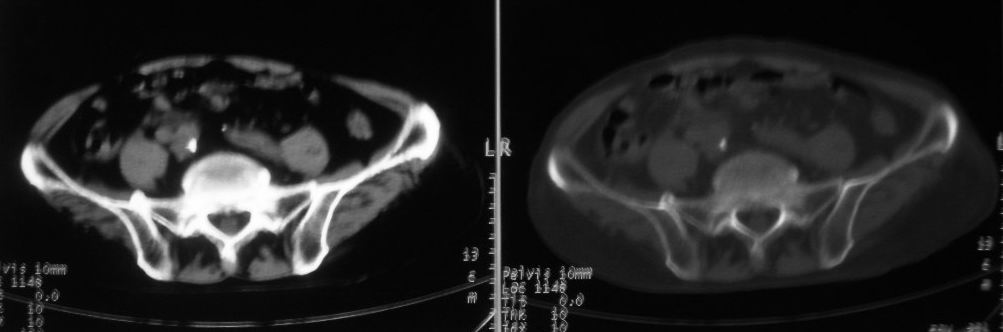

以下是引用zjzjr在2008-10-3 12:59:00的发言:[br]前列腺癌伴左髂骨\\腰椎转移可能性大.

以下是引用卜一在2008-10-3 13:40:00的发言:[br]前列腺癌!左髂骨\\腰椎转移?建议行全身骨扫描!

以下是引用深泽交通医院在2008-10-3 15:33:00的发言:[br]前列腺实性增大伴分叶状,与包膜间隙境界不清;椎体松质区间结节样密度影,考虑:前列腺癌,并椎体成骨性转移